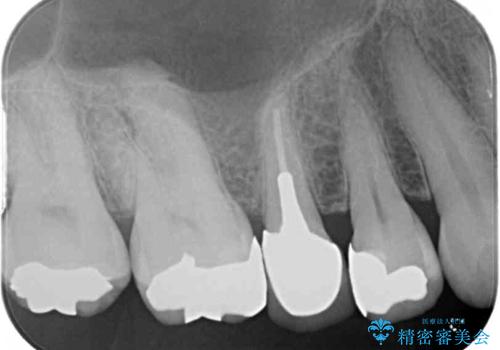

- 歯肉が退縮したためにクラウンの縁や歯根が見えてしまっていることを気にして来院された患者様です。

また、歯肉が黒く変色していることも気になるとのことでした。

仮歯に変える際に歯肉の一部を切除し、金属片による変色を除去した後、オールセラミッククラウンにて補綴することとしました。